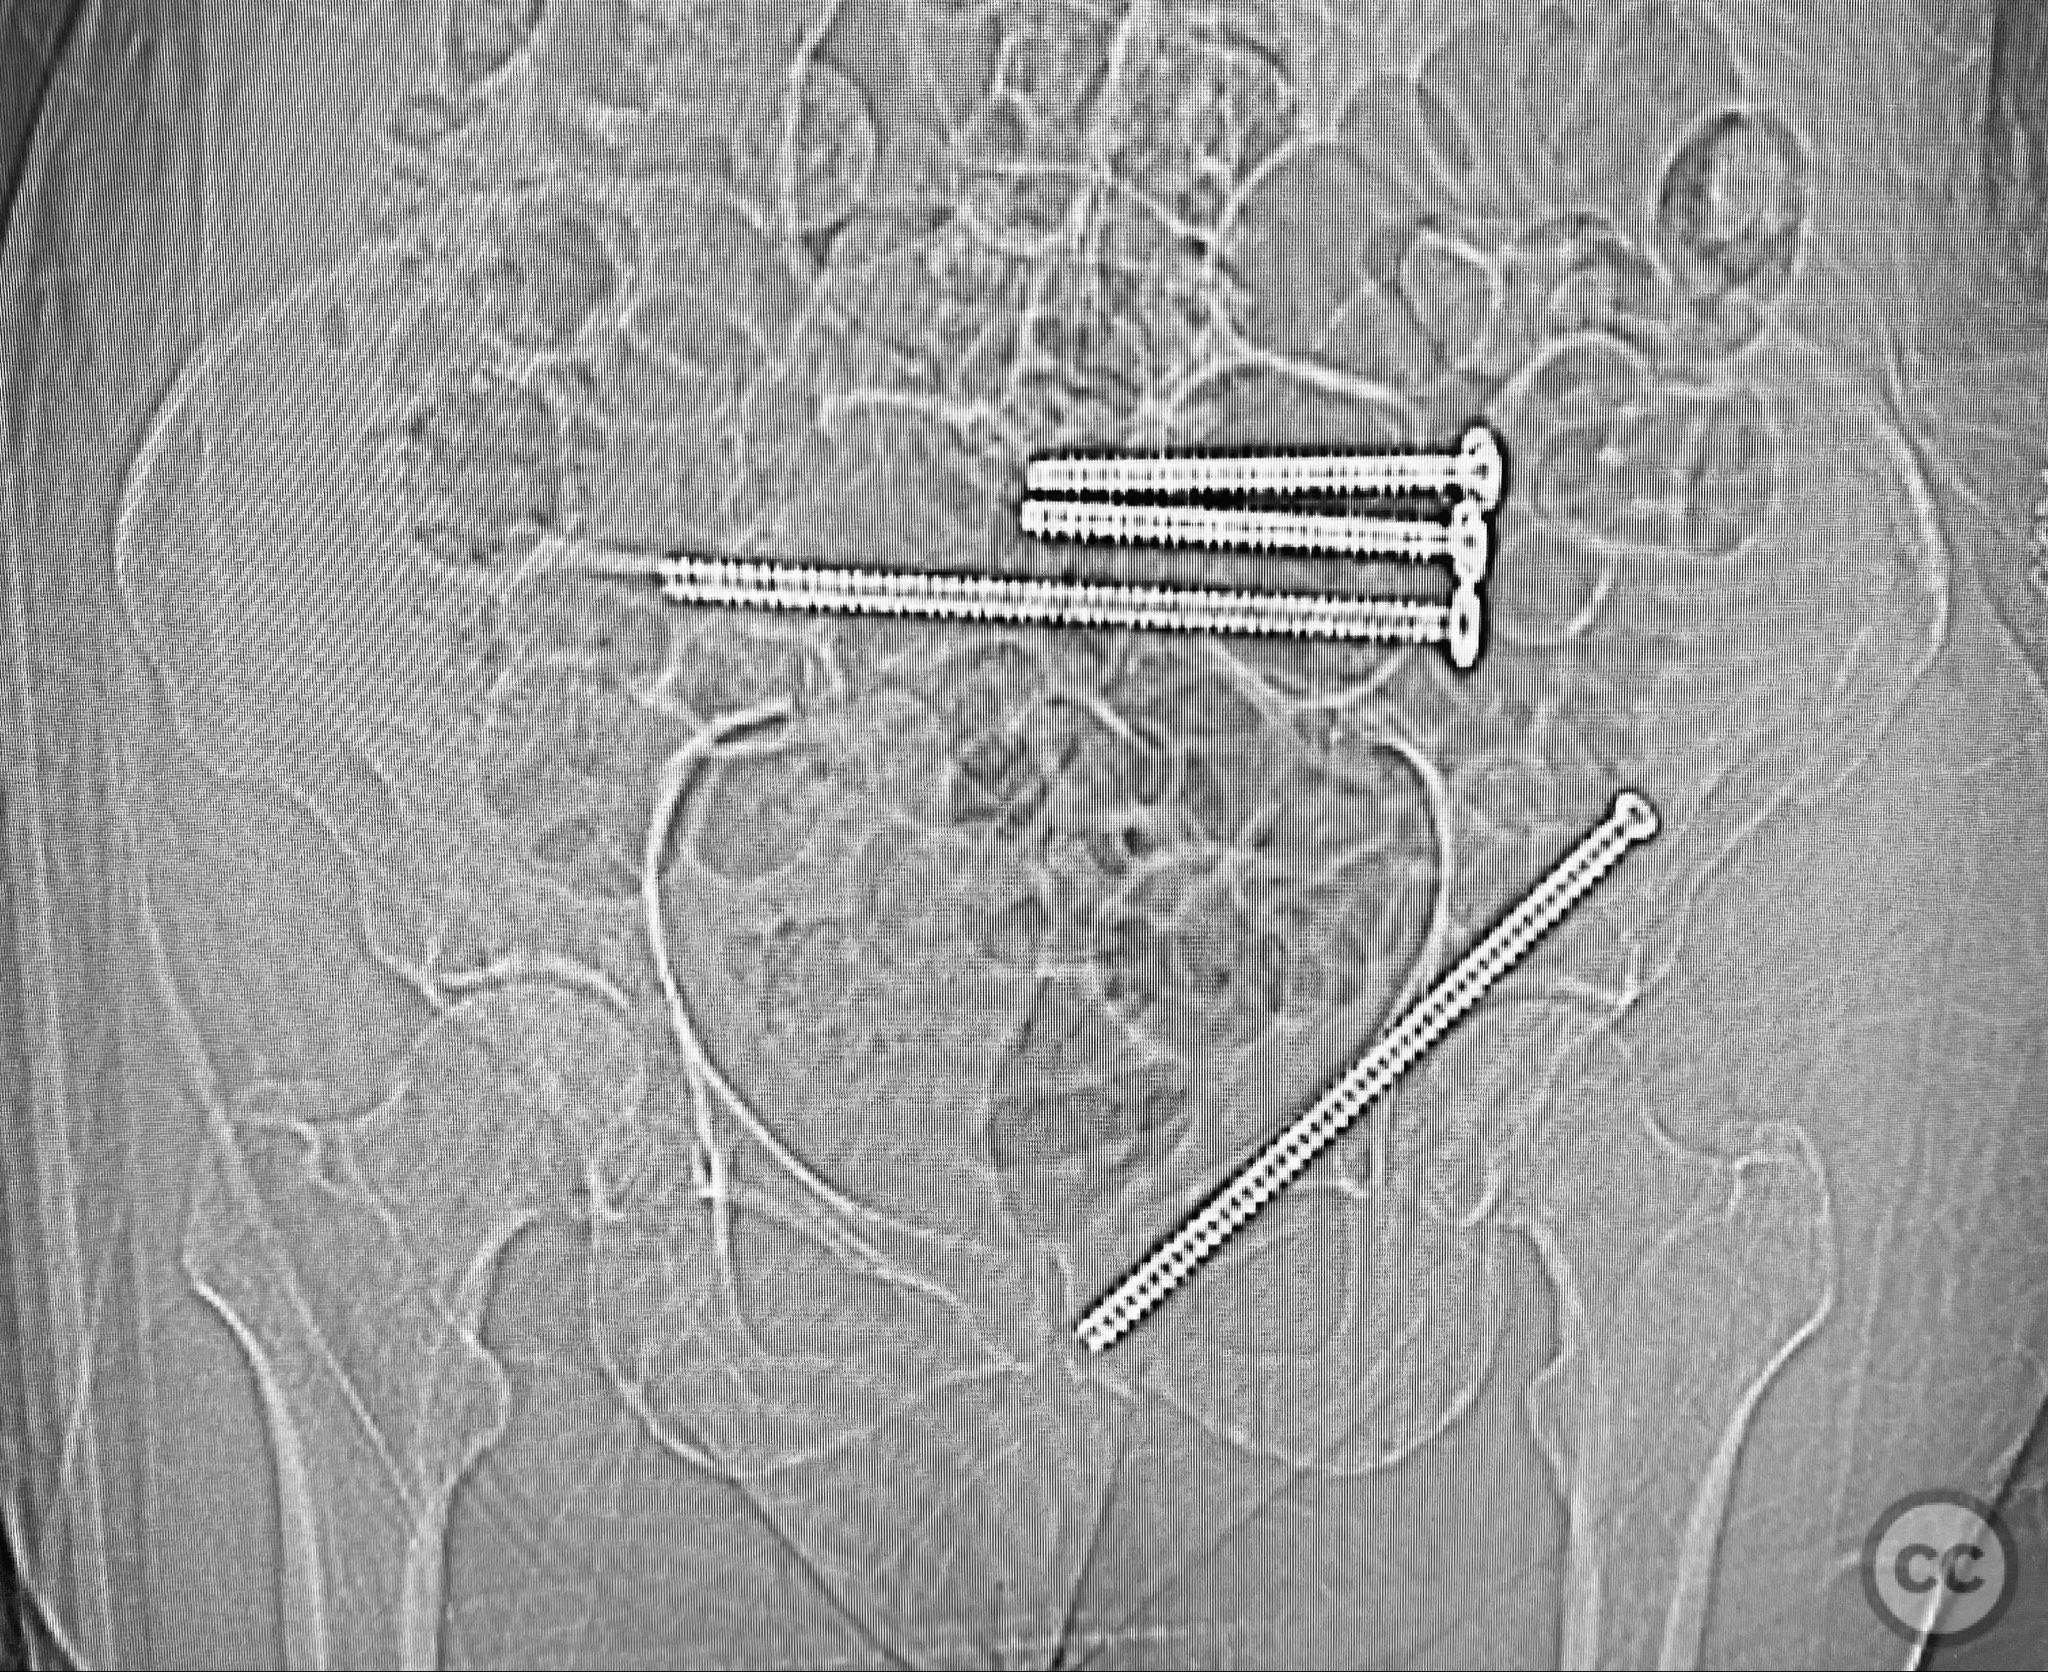

Anatomical surgical approach:  Percutaneous technique was employed. Small stab incisions were made over the lateral aspect of the pelvis. Under continuous fluoroscopic guidance, guidewires were advanced through the ilium into the sacrum (iliosacral region) and through the superior pubic ramus. Cannulated screws were then inserted over the guidewires, ensuring extra-articular and intraosseous positioning within the safe bone corridors as determined by preoperative CT analysis.

Intraoperatively, manual manipulation of the pelvis was performed to achieve improved reduction prior to fixation. The stability achieved by percutaneous screw fixation provided immediate symptomatic relief, allowing for early mobilization. The procedure emphasized meticulous attention to fluoroscopic imaging and preoperative CT planning to avoid neurovascular compromise and optimize screw trajectory within osteoporotic bone.

Orthopaedic implants used:   Cannulated iliosacral screw, cannulated pubic ramus screw